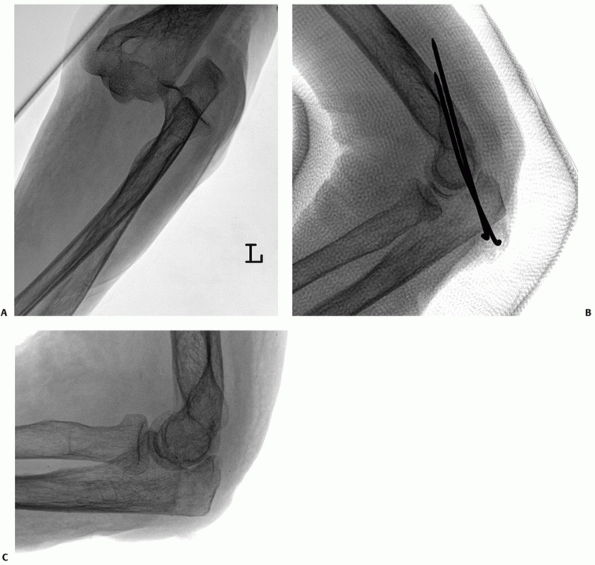

![]() |

FIGURE 32-24 A 35-year-old man who fell from four stories had an unstable simple elbow dislocation. A. Despite a hinged brace, the trochlea is perched on the coronoid process. B. The medial collateral ligament and common flexor muscles were avulsed from the medial epicondyle. C. The lateral collateral ligament and common extensor muscles were stripped off of the lateral epicondyle. D. Anteroposterior radiograph after reattachment of the soft tissues to the epicondyles shows concentric reduction.

Steinmann pins and a hinged external fixator is applied. There are

application should be followed (Fig. 32-26).

Kirschner wires are drilled across the ulnohumeral joint. Usually one